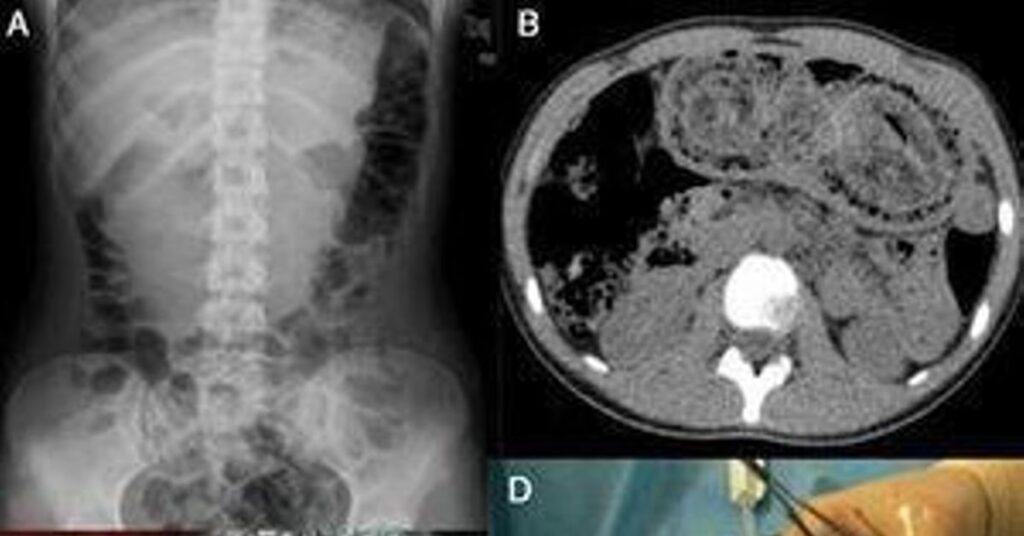

¿Cómo se Diagnostica el Síndrome de Rapunzel? La Búsqueda de la Evidencia Oculta

El diagnóstico del síndrome de Rapunzel, y en general de los tricobezoares, puede ser un desafío debido a la naturaleza oculta de la tricofagia. Sin embargo, una vez que la sospecha clínica surge, existen métodos radiológicos efectivos para confirmarlo.

- Radiografía abdominal: Puede mostrar signos indirectos de obstrucción o una masa inusual.

- Ecografía: Permite visualizar estructuras calcificadas, granulares o en forma de remolino de material sólido y gaseoso dentro del estómago.

- Tomografía Computarizada (TC): Es el método de elección para confirmar el diagnóstico. Con contraste oral, la TC puede revelar una imagen heterogénea, con material sólido y aire atrapado que ocupa la luz gástrica y se extiende a otras partes del intestino. Muestra claramente el tamaño, la forma y la extensión del tricobezoar.

El descubrimiento de un tricobezoar a menudo es una sorpresa para los médicos, ya que los pacientes rara vez mencionan su hábito de comer cabello. Es por ello que la sospecha clínica, especialmente en mujeres jóvenes con síntomas gastrointestinales inexplicables, es fundamental.